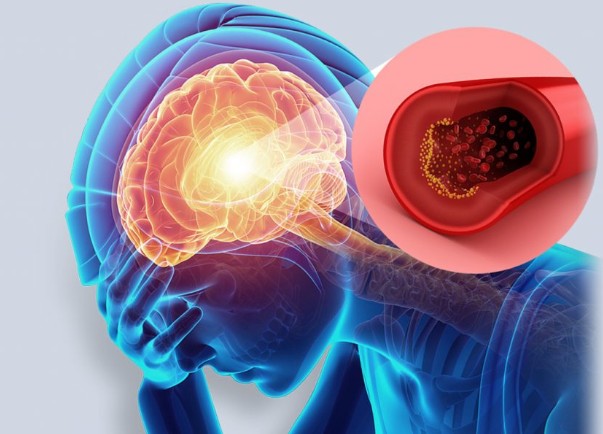

이때는 양팔을 들어보게 했을 때 한쪽이 내려가면 응급 상황을 의심해야 합니다.3. 갑작스럽고 심한 두통

기존에 경험해보지 못한 극심한 두통이나 ‘머리를 망치로 맞은 듯한’ 고통은

출혈성 뇌졸중(지주막하 출혈 등)의 전조일 수 있습니다.

특히 구토를 동반한 두통이라면 즉시 병원을 가야 합니다.